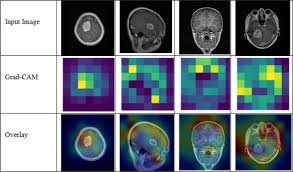

Enhanced Classification of Brain Tumors from MRI Scans using a Hybrid CNN-Transformer ModelData Engineering

(Accepted for IEEE QPAIN 2025 and possible inclusion in IEEE Xplore Digital Library, and indexed by Scopus and other indexing services.) Abstract—The study of brain tumors creates a paradox in neuro-oncology,…